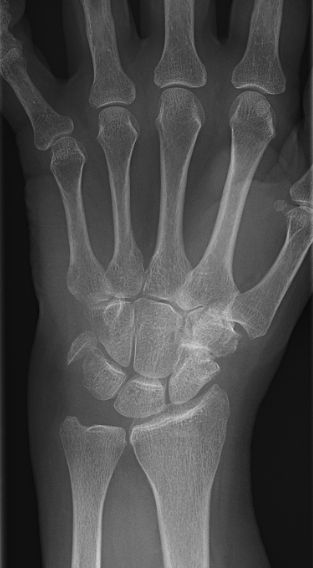

Exempel på luxation av pisiforme, har också fraktur i skafoideum. Utreddes även med DT, pisiforme exciderades av handkirurg.